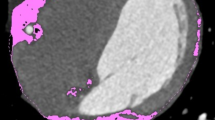

Measurements of adipose tissue were performed in a random subset of participants from the Framingham Heart Study (n=100) who underwent multidetector CT of the thorax (ECG triggering, 2.5 mm slice thickness) and the abdomen (helical CT acquisition, 2.5 mm slice thickness). Abdominal periaortic adipose tissue (AAT) was defined by a 5 mm cylindrical region of interest around the aortic wall; thoracic periaortic adipose tissue (TAT) was defined by anatomic landmarks. TAT and AAT were defined as any voxel between −195 and −45 HU and volumes were measured using dedicated semiautomatic software. Measurement reproducibility and association with anthropometric measures of obesity, and abdominal adipose tissue were determined.